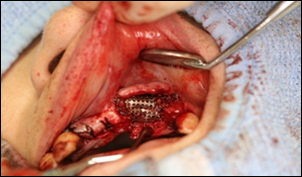

骨造成法

インプラントを埋めるための顎の骨の量が足りない場合に行う手術です。骨造成法には下記の種類があります。

GBR法

1:インプラントを入れた状態です。

骨が足りないためインプラント体が全て埋まらずに見えてしまっています。

2.1を上から見た図です

3.造骨に使用する補填剤です。

β-TCPという骨補填剤とPRPという血液から血小板を凝縮して作ったものと 自家骨を混ぜたものです。

4.チタンの膜を置いて歯ぐきと骨の間にスペースを作り、3の補填剤を入れます。

5.チタンの膜を骨の上に被せたところです。

真上からみた図

6.頬側から見た図

7.4ヶ月後にチタンの膜を取り除いたところです。

骨が新しく作られ、インプラント部が完全に埋まっていることがわかります。